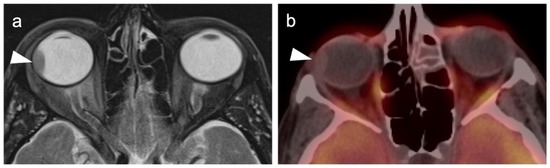

- Sharma, R.; Shah, P.; Narendran, V. Poor uptake of fluorodeoxyglucose in positron emission tomography-computed tomography scan for intraocular choroidal melanoma in Asian Indian Eyes. World J. Nucl. Med. 2016, 15, 53–55. [Google Scholar] [CrossRef]

- Reddy, S.; Kurli, M.; Tena, L.B.; Finger, P.T. PET/CT imaging: Detection of choroidal melanoma. Br. J. Ophthalmol. 2005, 89, 1265–1269. [Google Scholar] [CrossRef] [Green Version]

- Zurcher, K.S.; Houghton, O.M.; Shen, J.F.; Seetharam, M.; Roarke, M.C.; Yang, M. Nuclear Medicine and Molecular Imaging in Nodal Staging and Surveillance of Ocular Melanoma: Case Reports and Review of the Literature. J. Nucl. Med. Technol. 2021, 49, 275–280. [Google Scholar] [CrossRef]

- Orcurto, V.; Denys, A.; Voelter, V.; Schalenbourg, A.; Schnyder, P.; Zografos, L.; Leyvraz, S.; Delaloye, A.B.; Prior, J. 18F-fluorodeoxyglucose positron emission tomography/computed tomography and magnetic resonance imaging in patients with liver metastases from uveal melanoma. Melanoma Res. 2012, 22, 63–69. [Google Scholar] [CrossRef] [PubMed]